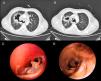

In 2017, he was admitted for fever and respiratory symptoms, with mediastinal lymphadenopathy conglomerates visualized on the chest computed tomography (CT). Successive sputum stains/cultures for mycobacteria and fungi and autoimmune markers were negative. The patient was treated with antibiotics and the corticosteroid dose was increased. Radiological images of the chest lesions showed deterioration, with thickening of the tracheal wall and necrotic masses, predominantly in the right hemithorax1,2 (Fig. 1A and B). Bronchoscopy (Fig. 1C and D) showed extensive areas of inflammation/necrosis in the main airways, with loss of wall structure and protruding fragments of cartilage. The pathology study reported granulomas, extensive necrosis, and hyaline membranes.2 Cultures for bacteria, mycobacteria, fungi, and panfungal PCR were negative.

(A and B) Chest CT showing significant concentric thickening of the tracheal wall and main bronchi, with vastly irregular tracheal and bronchial luminogram. Necrotic masses are also observed, mainly in the right hemithorax, contiguous with the bronchus of the right upper lobe. (C and D) Bronchoscopy images: (C) tracheal stenosis with friable mucosa and protrusion of fragments of cartilage; (D) division of left upper lobe and lower lobe bronchi, showing mucosa with mammilated areas.